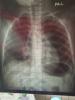

Девчонки,5 дней лечили пневмонию антибиотиками.Сейчас такой ренген,получше?

Я не врач в снимках не понимаю особо, но когда мы лечили пневмонию, после недели врач сказал, что она так быстро не проходит, нормальные лёгкие на снимке будут только в течении месяца, самое главное, что она пошла на спад, как то так было. Потому что я помню снимок увидела и тоже испугалась